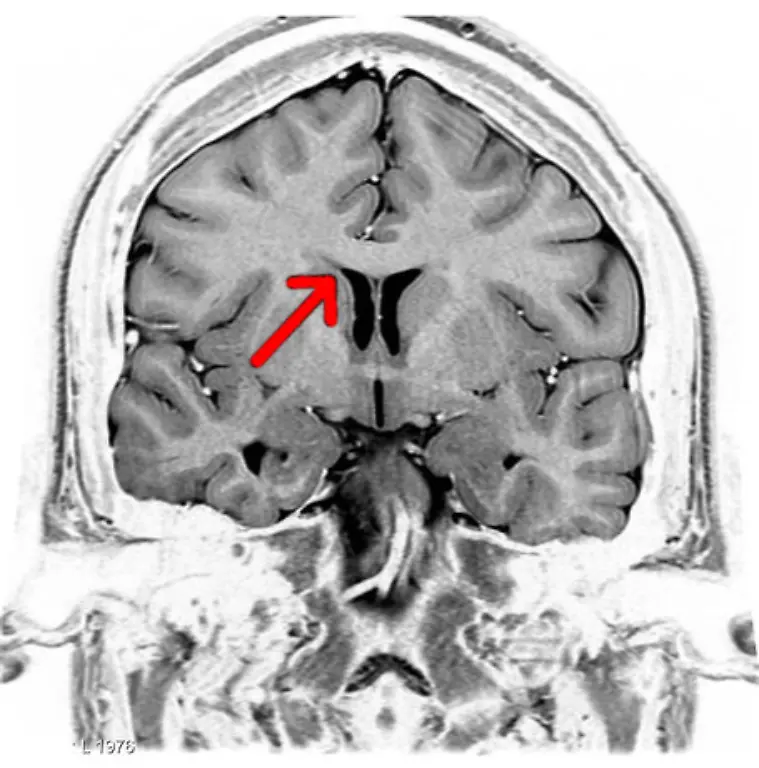

Egal, ob es ums Sehen oder Hören geht, ums Atmen, Sprechen, Rechnen oder Laufen: Stets sind es Milliarden grauer Zellen, die diese Fähigkeiten ermöglichen. Viele verschiedene Bereiche des Gehirns arbeiten zusammen, um die unterschiedlichsten Aufgaben zu lösen. Was wird von wo gesteuert? n-tv.de erklärt, was es mit Frontallappen, Mandelkern & Co. auf sich hat.